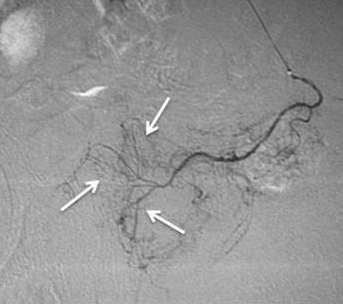

前列腺动脉栓塞的技术成功率=75%(9/12),双侧栓塞为9例(75%),单侧栓塞为3例(25%);单侧栓塞的原因是没有看见其中的一支动脉(prostatic asymetry),微导管不能沿导丝前进(No microcatheter progression over the wire)和膀胱下动脉夹层(IVA dissection)